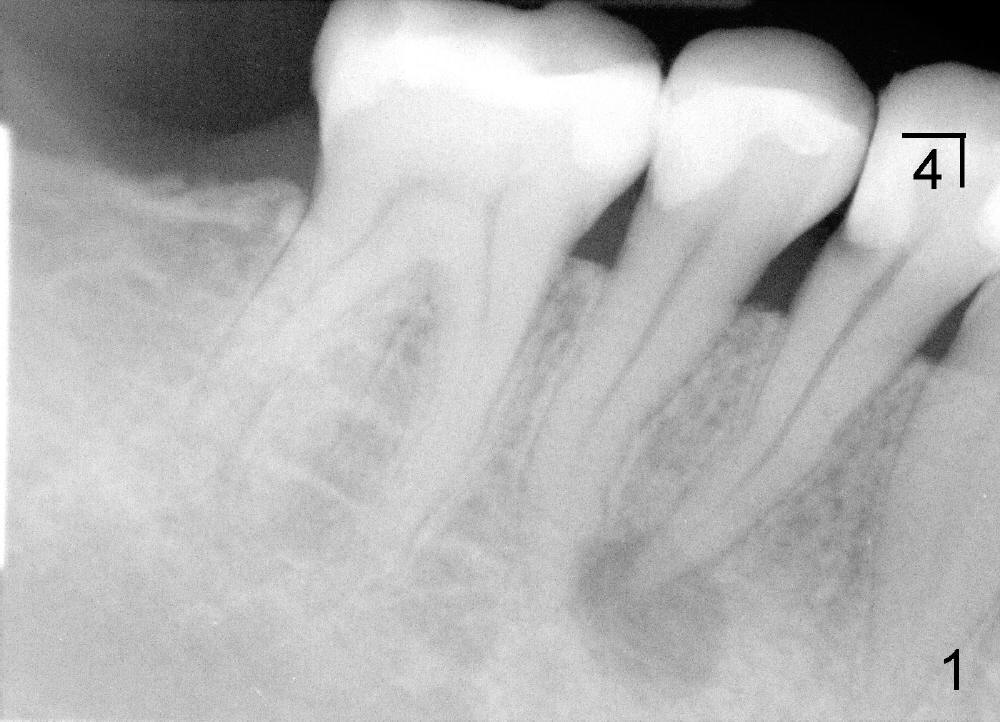

言归正传,五十一岁女人昨天第一次来诊所就诊(急诊),去年十一月在别的诊所右下第一双尖牙远中做树脂修复,术中发现穿髓,术后不时,现在颊侧根尖有压痛,根尖片显示根尖阴影(图一),多谢田智敏几天前指导,现在看根尖片,多注意些根尖弯曲,根管治疗中,不由自主地事先弯曲细小根管锉(hand files),一点没有问题,一直使用到二十号根管锉,根管长度21.5毫米(working length (WL)),下颌第一双尖牙一般单根,属于大根(方老师见解),接着用40/.06 rotary file(用了几年rotary files,大多数根管治疗好像不需要按部就班地使用crown down 技术:例如先用40/.10 rotary file,然后40/.08, 再用40/.06),问题在于这个rotary file只能进入十七毫米,突然在梦中清醒:根管是弯曲的。由于急诊时间紧,接着使用30/.04 rotary file,能达到WL,然后让漂白液浸泡根管十到二十分钟,去处理另外一个病人。回来后用30/.06 rotary file也没有问题,反复冲洗后,吸干根管,放置Ca(OH)2糊剂(图二:超冲些)。如果下次病人回来时没有疼痛症状,冲洗掉Ca(OH)2糊剂,便使用30/.06主牙胶尖充填,重新做树脂修复(老的有leakage),如果新的树脂没有leakage(拍摄X光片),我可能同意病人意见:不做牙冠。仿佛这例牙冠必要性不大。方老师,田兄,或者任何人:您们怎么处理这样病例?图三是以前拍摄的全景片,显示左下第二双尖牙根尖够弯曲的。